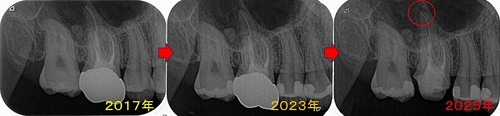

過去からのレントゲンを見ると

口蓋根の根尖に前は無かった根尖病変が現れています。

綺麗に口蓋根の根尖病変は治ってくれています。

綺麗に治ってくれたので、次にセラミッククラウンの治療に入って行きます。